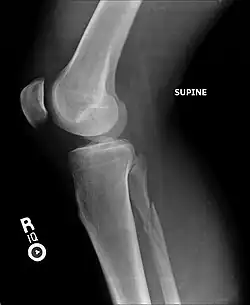

A Maisonneuve fracture may be a simple fracture or comminuted fracture:[8]

• A simple fracture, in the case of a Maisonneuve fracture, only refers to the fibula being broken in one place without any damage being done to the surrounding tissues.

• A comminuted fracture is when the bone is broken in more than two places.

X-ray, CT, or MRI scans can be used to diagnose the extent of the Maisonneuve fracture's damage and determine whether it is a simple or comminution fracture.[8] During diagnosis, a supination-external rotation pattern of injury may also be concluded if there is an isolated fracture of the posterior tubercle of the tibia.[9]